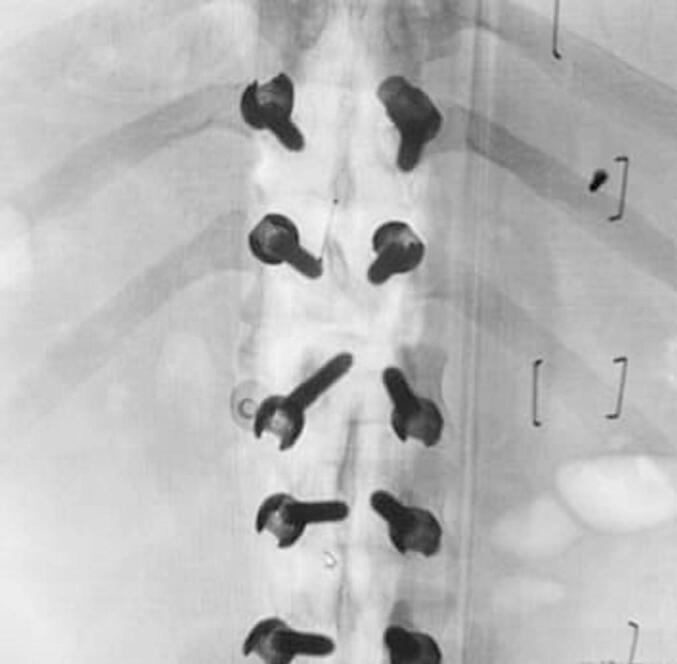

We performed open surgical methods by using interbody fusion modalities usually in patient's with stable vital signs. This intervention could be the priority in managing patients with a rare case of anterior spondyloptosis. A visual analog Scale (VAS) was used for monitoring the degree of pain, and Oswestry Disability Index (ODI) questionnaire for evaluating the outcome for low back pain.

我们通常对生命体征稳定的患者采用椎间融合方式进行开放手术。对于罕见的前位椎体滑脱病例,这种干预可能是治疗患者的首要选择。采用视觉模拟评分法(VAS)监测疼痛程度,采用奥斯威斯残疾指数(ODI)问卷评估腰痛的治疗效果。